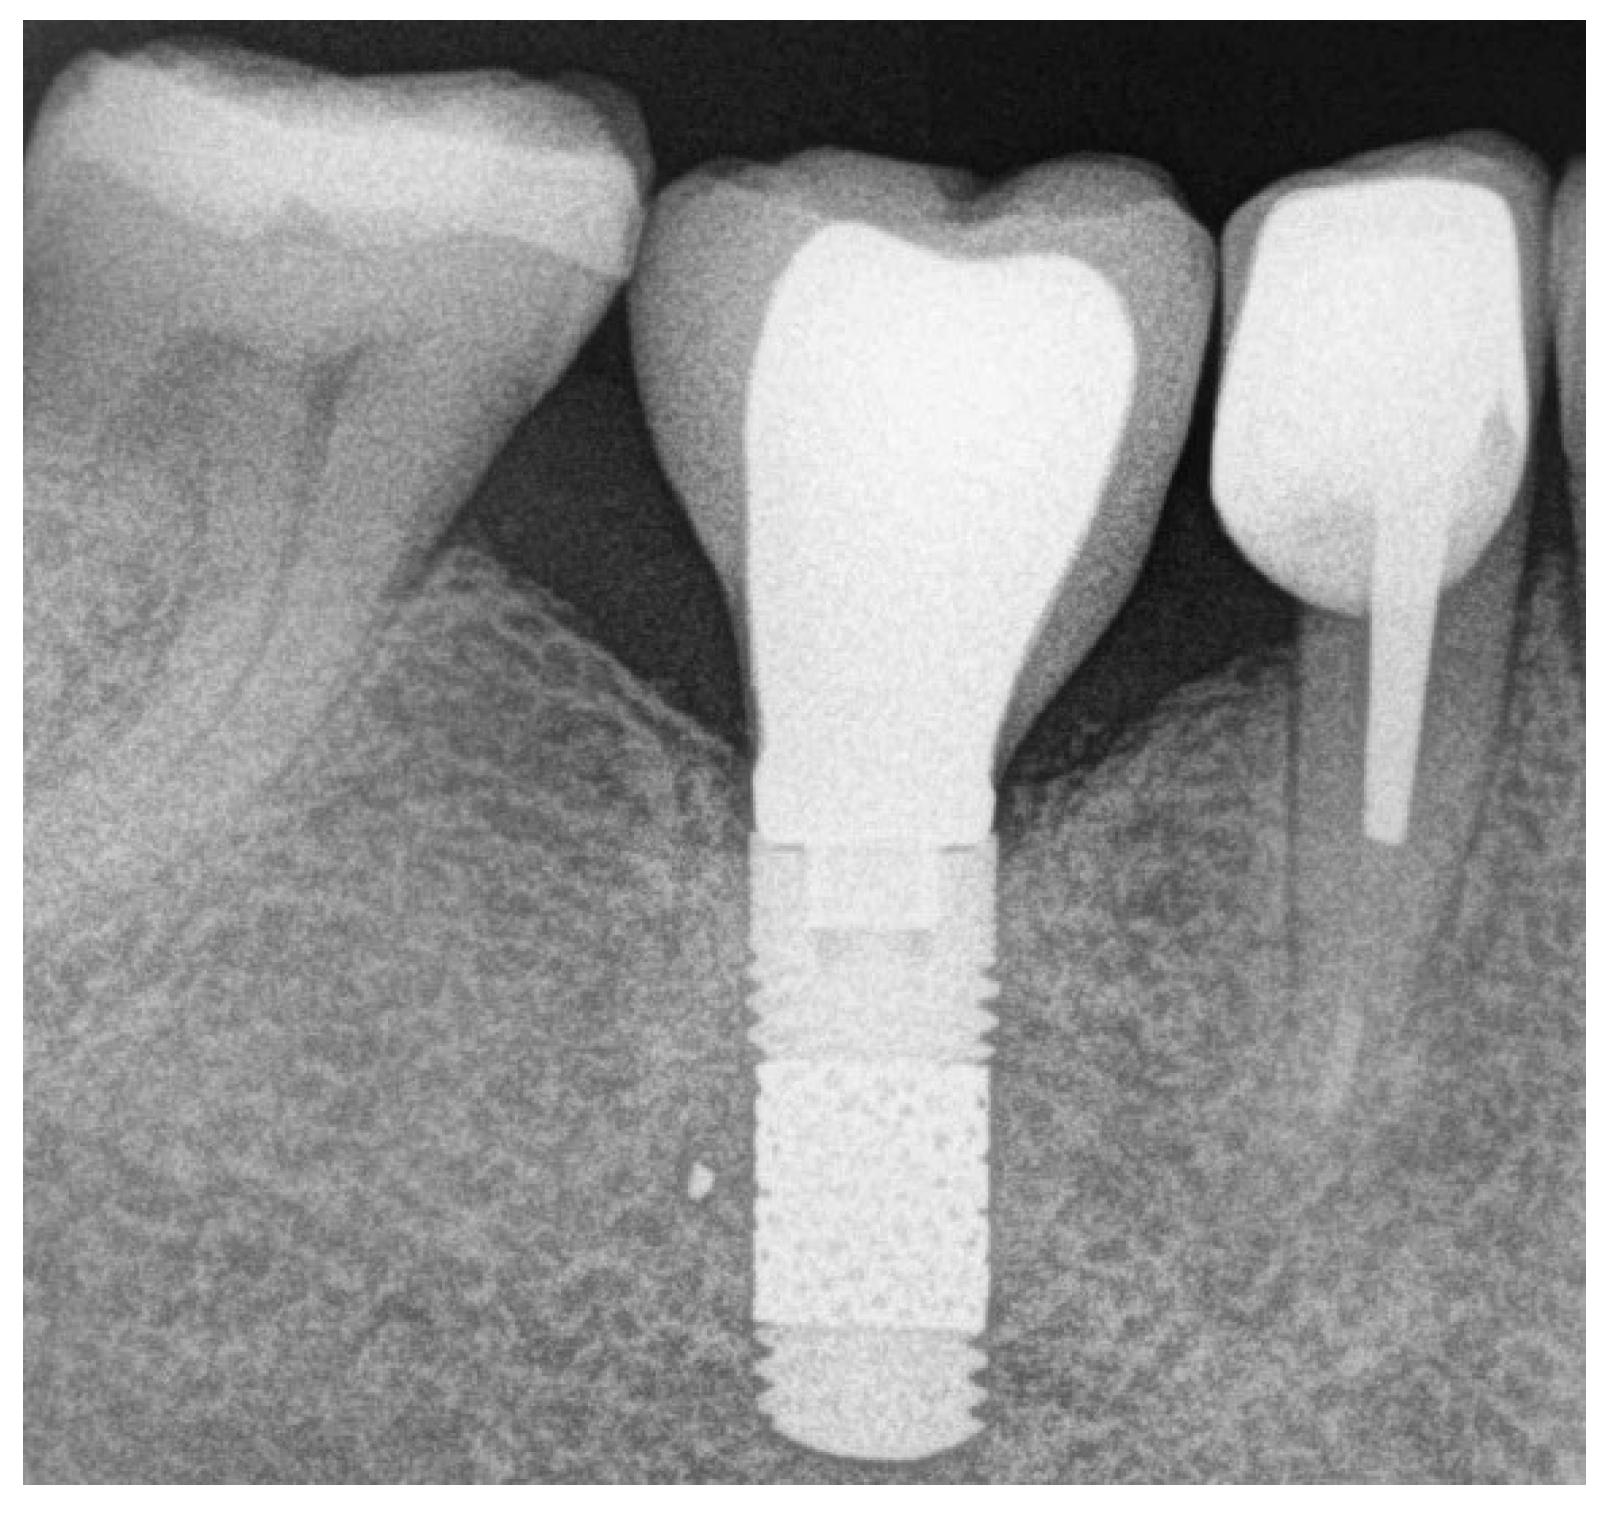

- Bone level changes were evaluated by comparing the measurements at baseline (on the day of prosthesis delivery) with those at follow-up visits. Measurements were obtained with an intraoral radiograph that depicted the vertical distance between the implant shoulder and the most coronal bone contact with the implant surface at mesial and distal sites. All the intraoral radiographs were taken using the parallel technique with an individual tray to ensure reproducibility. Measurements were always performed by the same experienced operator (S.B.) through the software ImageJ version 1.46 (National Institutes of Health, Bethesda, MD, USA), using the known TM implant diameter for calibration. The mesial and distal values were averaged to have a single value per implant.